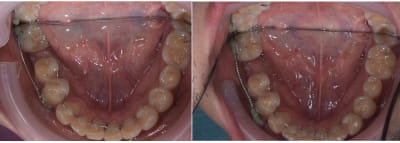

Suivis à 3 mois.

Et un autre cas 5 semaines d'interval entre les deux photos.

Enfin là j'ai seulement à ouvrir les espaces pour les implants.

Le truc marrant c'est que pour ce cas, la patiente c'est plein que l'espace ne s'ouvrait pas et que les dents de devant développé un encombrement. Je lui ai montré les photos initial et en court de traitement pour lui prouvé que ses dents était encombré depuis le départ, comme expliqué lors de la consult initial.

Je lui ai indiqué que l'encombrement pouvait être résolut simplement par des gouttière, bague vestibulaire/ lingual mais une fois qu'elle à admit qu'elle était comme ça depuis le départ, plus aucun intérêt pour aligner les incisives.

Patient vue aujourd'hui. Quatre mois de traitement .